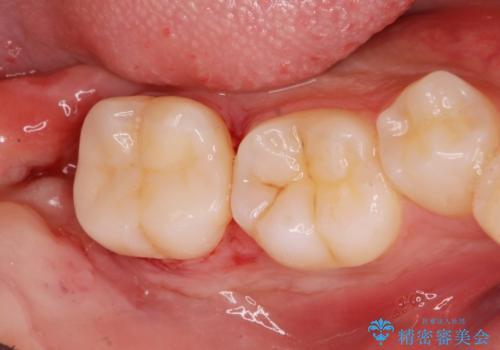

大きく歯が欠けた。 外科処置を行ったセラミック治療

歯冠長延長術をおこなったアプローチの難しい虫歯治療

奥の虫歯 ジルコニアクラウンでの修復